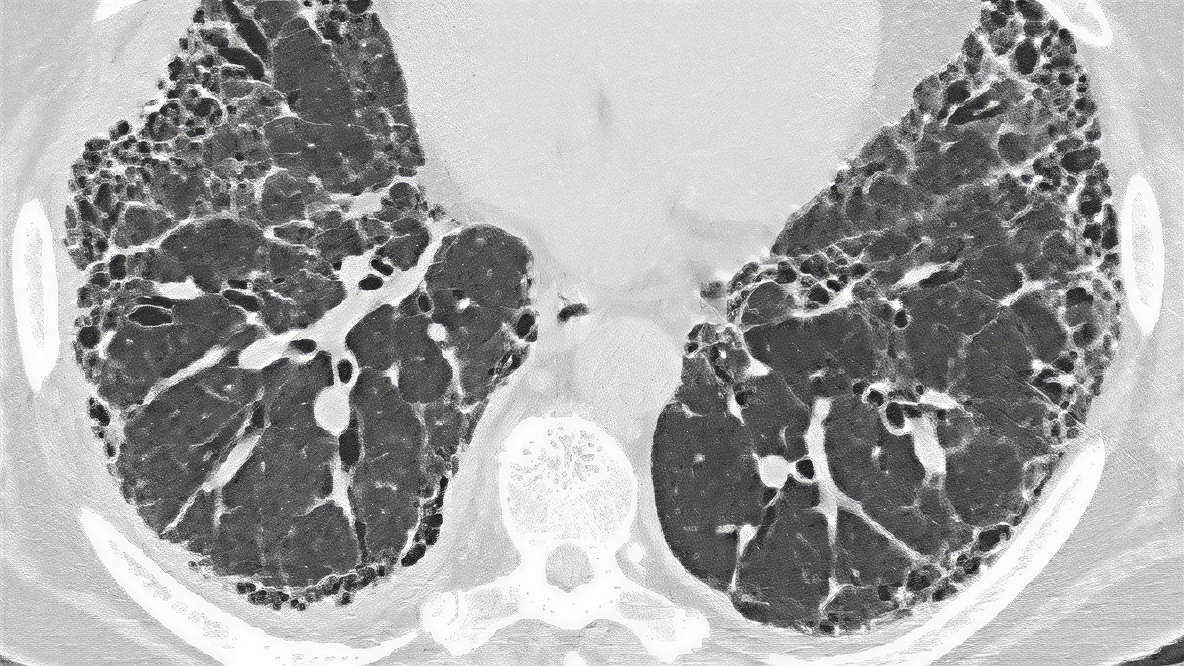

Cechy odpowiadające obrazowi UIP w badaniu HRCT:9

• Obraz plastra miodu

• Zmiany siateczkowe

• Trakcyjne rozstrzenie oskrzeli

Ocena pod kątem IPF w badaniu HRCT

UIP w HRCT

Wytyczne ATS/ERS/JRS/ALAT zalecają pewne rozpoznanie IPF, jeśli ocena kliniczna pacjenta wskazuje na IPF, a badanie HRCT wykazuje definitywny lub prawdopodobny obraz UIP (zalecana biopsja warunkowa).3

U pacjentów z włókniejącym HP w badaniu HRCT zazwyczaj występują zmiany siateczkowe, trakcyjne rozstrzenia oskrzeli i utrata objętości; mogą także występować zmiany typu „plastra miodu”:20